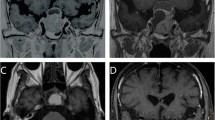

Example of hypofractionated SRT using CyberKnife for a patient with growth hormone-secreting pituitary adenoma. a Gadolinium-enhanced coronal MRI before SRT and the visual field test. b CyberKnife planning. c Gadolinium-enhanced coronal MRI and the visual field test 11 months after SRT. d Gadolinium-enhanced coronal MRI 120 months after SRT

In the present study, there were many cases in which tumor shrinkage or complete response was observed after SRT when evaluated by diagnostic imaging; however, the effects observed on these images were not reflected in biochemical data. Figure 3 shows one such case. This was a 25-year-old woman with acromegaly who had visual field abnormalities after multiple surgeries and drug therapy, and was then judged to be inoperable. Before hypofractionated SRT, GH was 3.5 ng/ml and IGF-1 was 310 ng/ml. She underwent hypofractionated SRT using CyberKnife with 31.7 Gy in 5 fractions to her 12.4 cc tumor. Eleven months after hypofractionated SRT, the tumor achieved a partial response, and improvements were noted in the visual field. At 120 months, the tumor achieved a complete response when rated by diagnostic imaging. However, hormone levels failed to completely satisfy the Cortina consensus (GH 5.2 ng/ml, IGF-1 305 ng/ml). Thus, in the present study, there were many cases in which the control of a macroscopic tumor did not satisfy the Cortina consensus criteria. Even when tumor volumes are controllable by hypofractionated SRT, achieving the suppression of GH appears to be difficult with this therapy alone. Although the possibility that hormones are produced by another co-existing microscopic tumor cannot be ruled out, the satisfactory control of symptomatic GH-PA requires multidisciplinary treatments, involving a combination of surgery, drug therapy, and irradiation. Landolt et al. [36] reported that patients in whom drug therapies were stopped before SRS had improved hormonal control than those who continued drug therapies. Although that was a small retrospective nonrandomized study, separating the two groups may be better considered in the future study. The conventional belief that complete endocrinological remission is achievable with radiotherapy alone needs to be reevaluated.